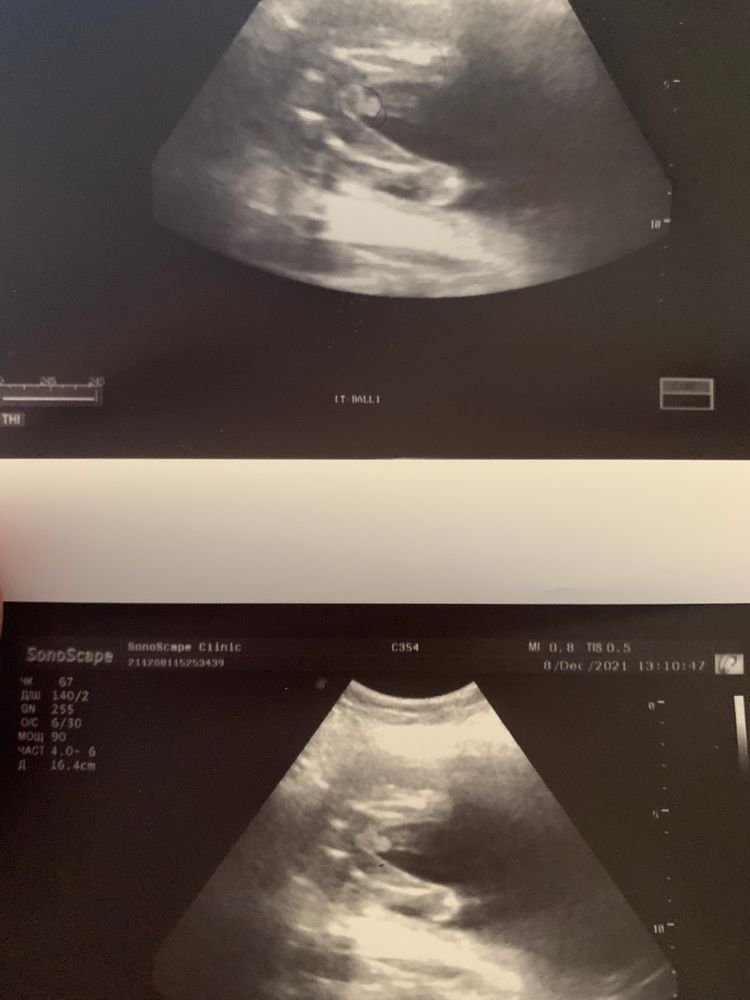

Мальчик или девочка

Это пацан, видно же машонку. Я была на узи в 20+ недель для определения пола, мне точно такое же фото показывали:)

У девочки губки, две полосочки. А тут на мошоночку похоже))

Мне кажется мальчик. Мне предполагают девочку, выглядит на УЗИ по другому.

vitaminka, а мне вот хочется девочку вот и пытаюсь что то разглядеть 🤣🤣просто со старшим сыном там прям так четко все было видно яички а тут не так четко ! Ну мне скоро ещё на узи идти посмотри что там скажут !

Екатерина Курлейко, а мне наоборот, вроде уже парня больше хочется. А предполагают девчонку с 10 недели 😂 завтра скрининг, может поточнее скажут. Сына в 11 уже точно увидели.